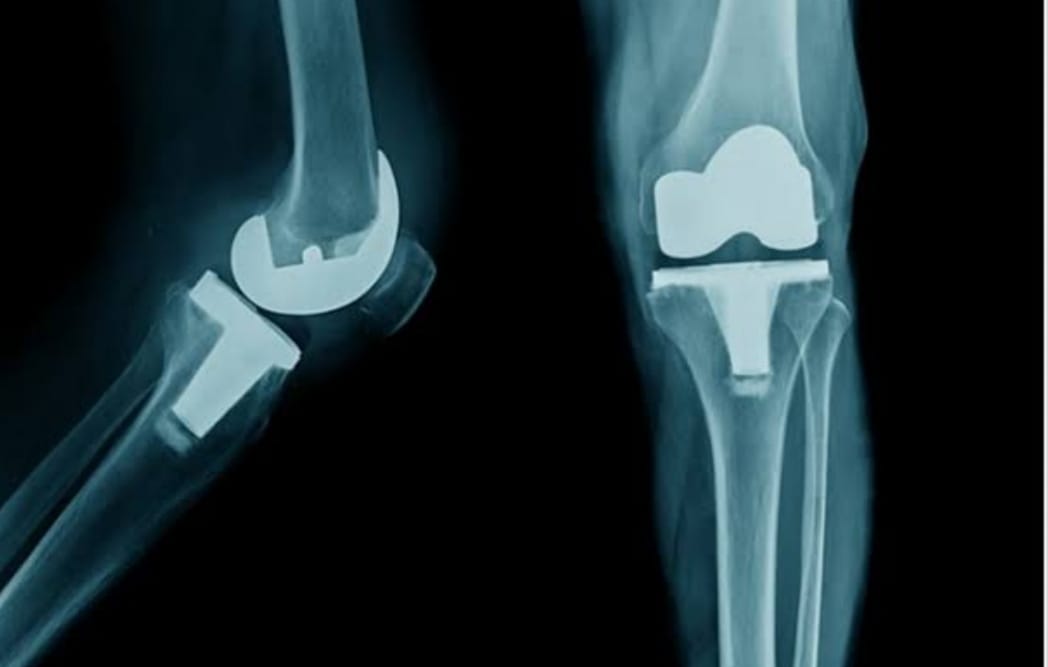

The Veer Hospital provides effective and high-quality healthcare services with 20+ departments, 16 special units and 50+ physicians. We offer an up-to-date medical approach in an ethical and reliable environment. We maintain our reputation in the health sector with our experienced medical staff who continuously improve qualified healthcare with an uncompromising focus when it comes to proficiency and academic values.